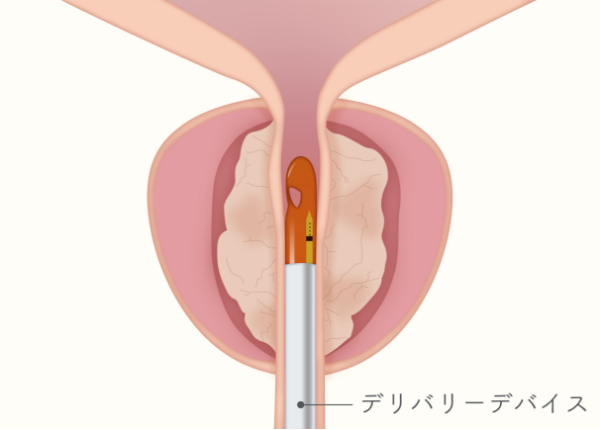

どのような手術なのか

Rezumシステムは、内視鏡を用いて尿道から入り、水蒸気を利用して前立腺肥大症を治療する医療機器です。

肥大した前立腺組織内に103℃の水蒸気を9秒間噴霧し、組織を約70℃まで上昇させることで組織を壊死させます。